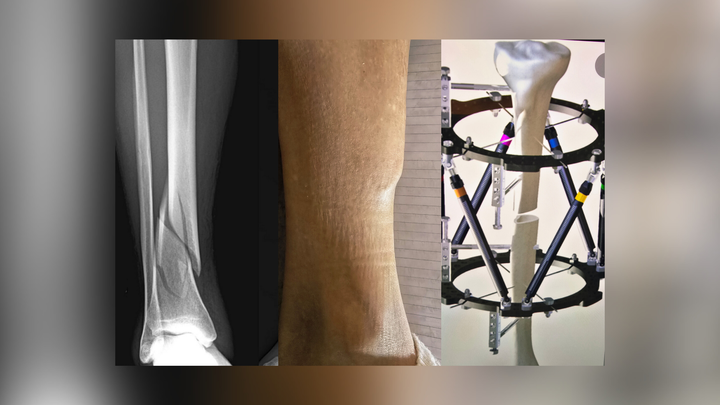

Years ago, she suffered a tibia injury that did not receive appropriate care at the time. As a result of poor treatment and incorrect healing, the bone healed improperly. Over the years, this caused progressive deformity in her skeletal structure from her hips down, affecting her alignment, mobility, and quality of life.

After extensive evaluations, doctors determined that corrective surgery is now the only option. She will need a complex tibial reconstruction using a Taylor Spatial Frame, an external fixation device that slowly grows new bone and rotates the leg back into its correct anatomical plane. This is not a short process — she will need to wear the frame for 12 to 15 months, followed by additional rehabilitation.